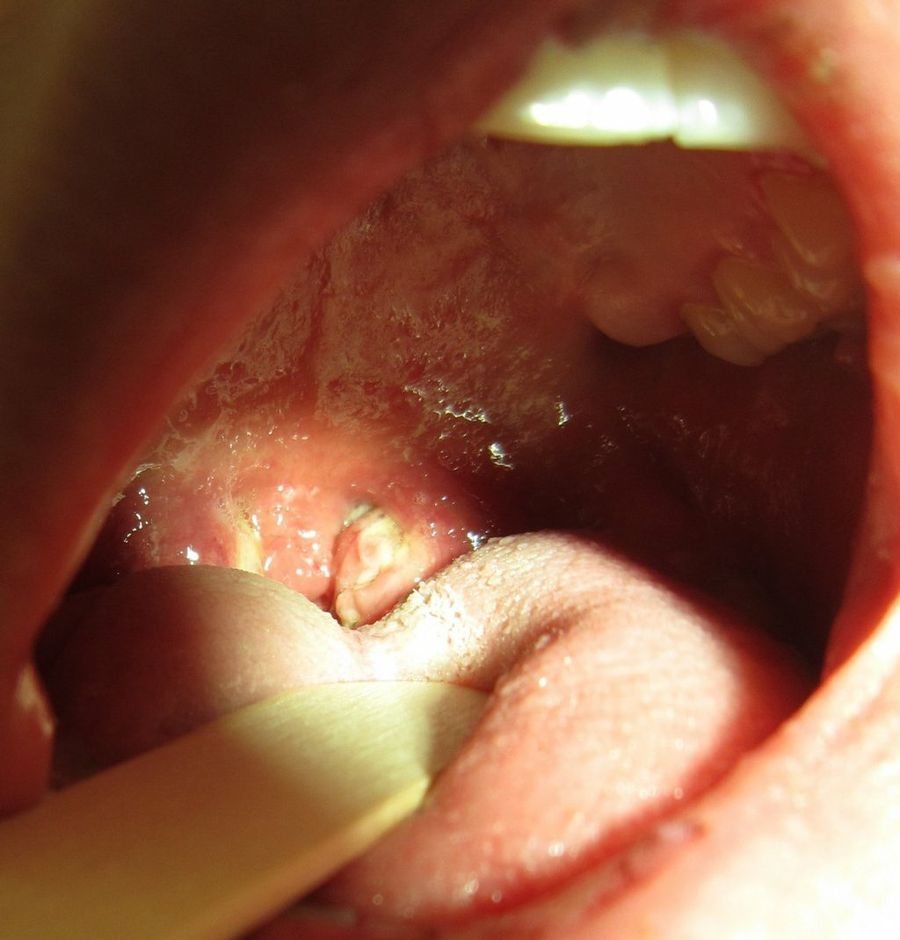

Por otro lado, la revista de oncología The Lancet, alertaba hace unos años sobre el vínculo estrecho entre infecciones y cáncer. Así es, esta prestigiosa publicación revelaba datos bastante preocupantes: "1 de cada 6 tumores está causado por una infección".

Parece mentira que algo tan 'evitable' como una infección pueda aparecer en las encuestas como causa primordial. Pero sí, lo hace, y de tal forma que "1,5 millones fueron debidas a una infección potencialmente prevenible y tratable". Así, la diferencia entre regiones resulta evidente, siendo el área más afectada el África Subsahariana. "Incrementar la cobertura de vacunas debería ser una prioridad para los sistemas de salud en países con una alta carga de estas infecciones", concluye la cabecera especializada.